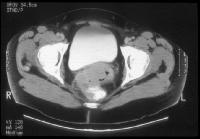

Cervix, cancer. Clinical stage IIb cervical carcinoma . The parametrial invasion is depicted with CT as loss of definition of the cervical contours accompanied with increased attenuation and prominent soft-tissue stranding in the parametrial fat. Parametritis can result in similar findings. The cervix shows ill-defined hypoattenuation, but the tumor is not clearly delineated. Cervix, cancer. CT demonstrates a markedly enlarged lymph node at the left pelvic sidewall. This finding is consistent with pelvic lymph node metastasis, which is indicative of stage IIIb disease. The cystic consistency is not unusual for metastatic cervical carcinoma. The primary tumor is well depicted as a hypoattenuating, circumscribed mass. A cyst is present in the anteriorly located left ovary.